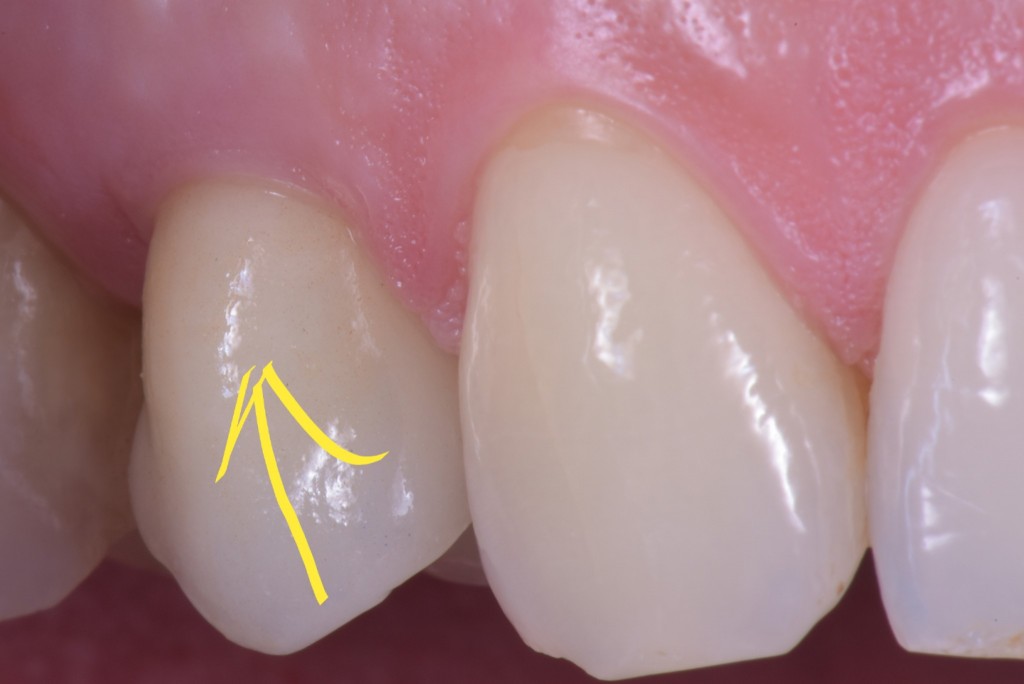

corso gestione tessuti molli - guarigione 1

corso gestione dei tessuti molli - guarigione 2

Ti mostro la foto a sette giorni per due motivi.

• La bellezza di una chirurgia si valuta dalla guarigione a sette giorni. Se aspetti 2 anni, alla fine anche una chirurgia di merda guarisce.

• Ho operato la paziente 7 giorni fa e non ho foto più recenti ma penso che concorderai con me che dopo una guarigione così difficilmente avremo delle sorprese.

Come puoi vedere abbiamo risolto completamente il deficit dei tessuti molli che era stato lasciato dopo le precedenti terapie e…

… posto le basi per una nuova riabilitazione definitiva che si possa definire esteticamente degna dei tempi in cui abbiamo la fortuna di vivere.